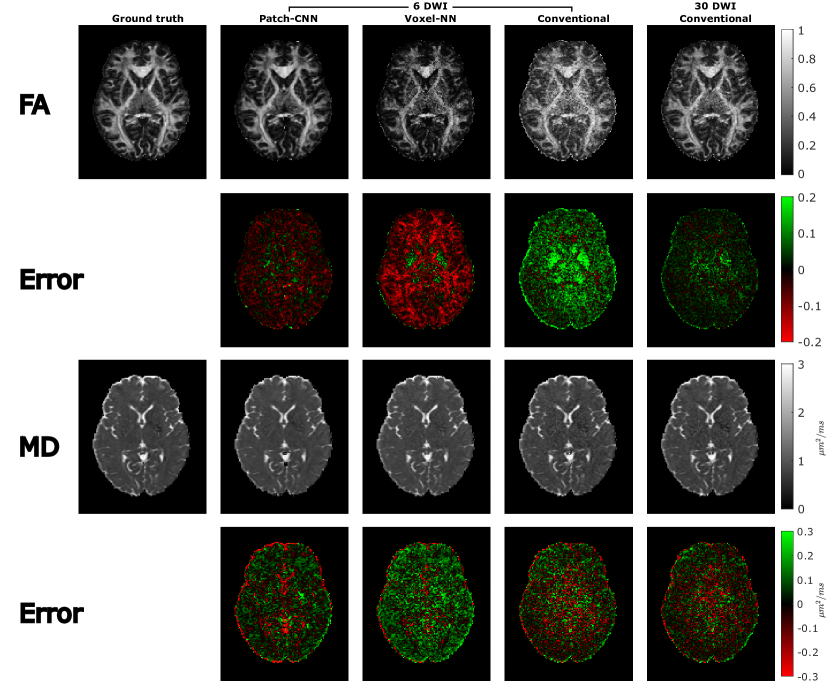

Figure 4: Scalar parameter (FA and MD) estimation are shown with their corresponding difference maps. Patch-CNN estimates less grainy and more accurate images for both MD and FA when comparing against the model fit and Voxel-NN. The improvement is larger in FA estimation.

The estimation performance on scalar measures derived from the diffusion tensor is shown in Figure 4. Axial slices of the estimated FA and MD are shown above their error maps. Qualitatively, Patch-CNN performs the best of the six directional estimations because it is the most similar to the ground truth image as well as having the least amount of noise. For FA estimation, conventional fitting largely overestimates the FA whereas Voxel-NN largely underestimates the FA. Only Patch-CNN estimates FA with far greater accuracy. Figures 2c and 2d further affirms that Patch-CNN outperforms conventional fitting with twice as many DWIs.